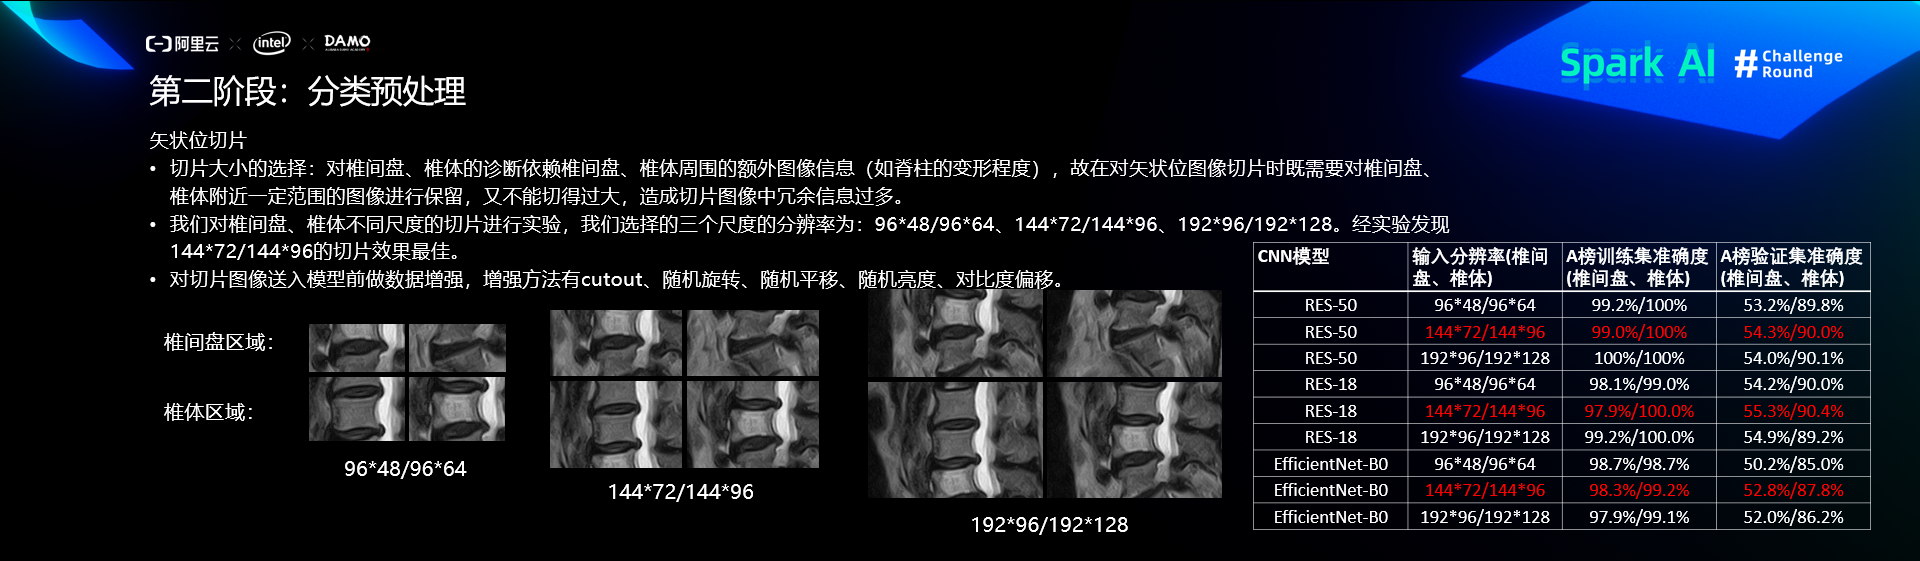

预处理